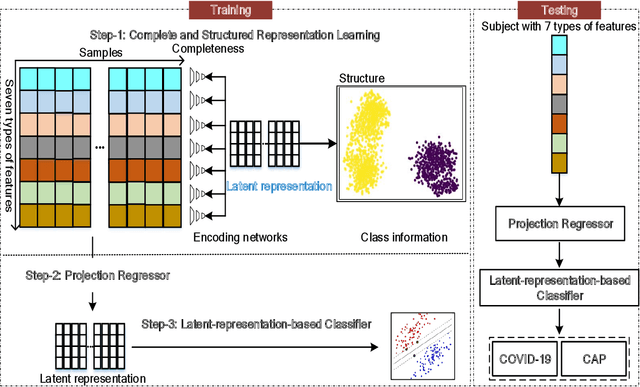

Recently, the outbreak of Coronavirus Disease 2019 (COVID-19) has spread rapidly across the world. Due to the large number of affected patients and heavy labor for doctors, computer-aided diagnosis with machine learning algorithm is urgently needed, and could largely reduce the efforts of clinicians and accelerate the diagnosis process. Chest computed tomography (CT) has been recognized as an informative tool for diagnosis of the disease. In this study, we propose to conduct the diagnosis of COVID-19 with a series of features extracted from CT images. To fully explore multiple features describing CT images from different views, a unified latent representation is learned which can completely encode information from different aspects of features and is endowed with promising class structure for separability. Specifically, the completeness is guaranteed with a group of backward neural networks (each for one type of features), while by using class labels the representation is enforced to be compact within COVID-19/community-acquired pneumonia (CAP) and also a large margin is guaranteed between different types of pneumonia. In this way, our model can well avoid overfitting compared to the case of directly projecting highdimensional features into classes. Extensive experimental results show that the proposed method outperforms all comparison methods, and rather stable performances are observed when varying the numbers of training data.